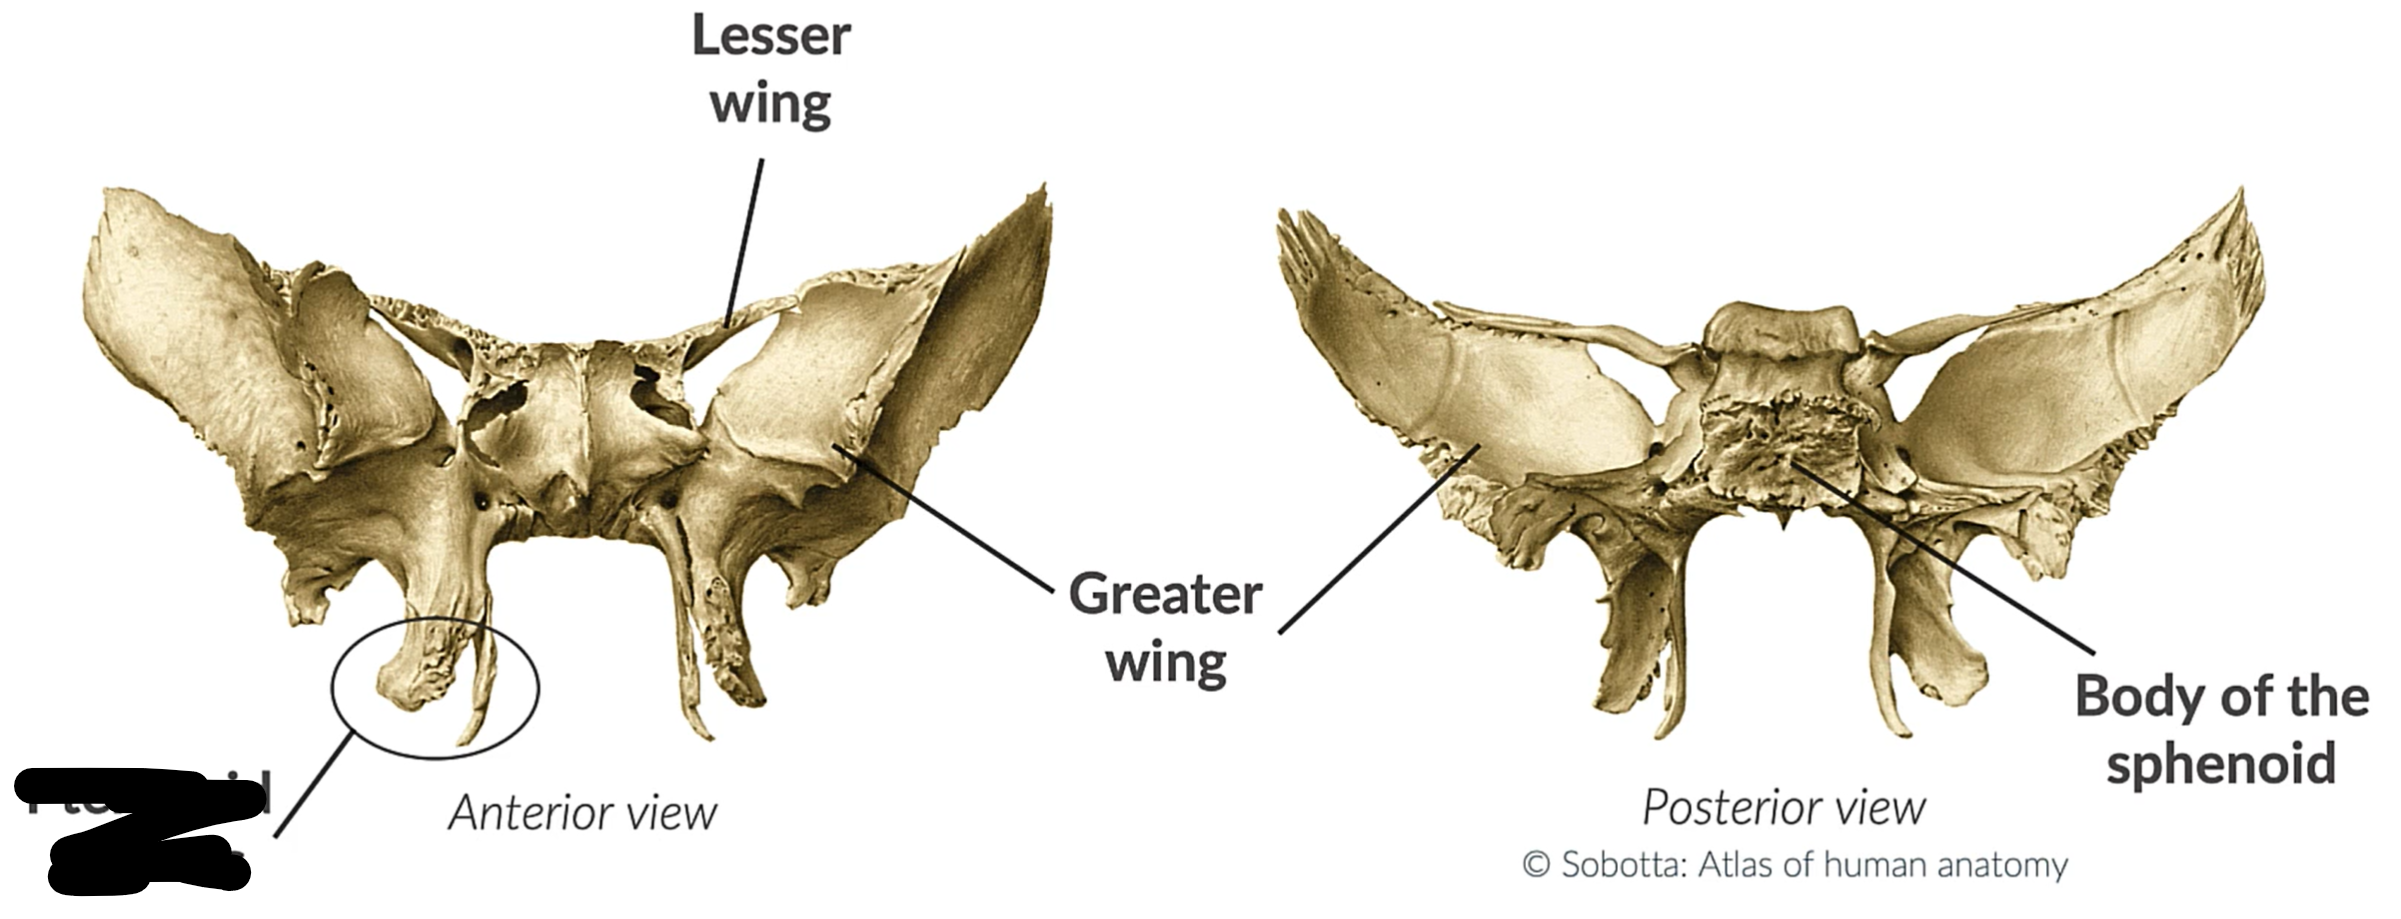

What bone is this?

Sphenoid bone

Lesser wing

Greater wing

Pterygoid process

Body sphenoid bone